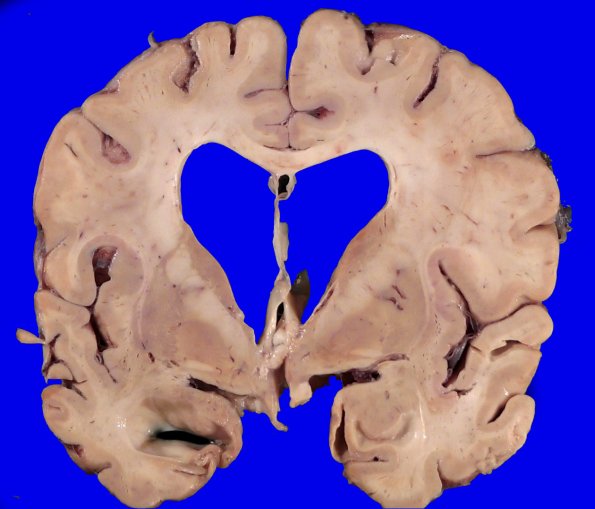

The thickness of the frontal cortex looks generally well preserved although the ventricular dilatation is out of proportion.